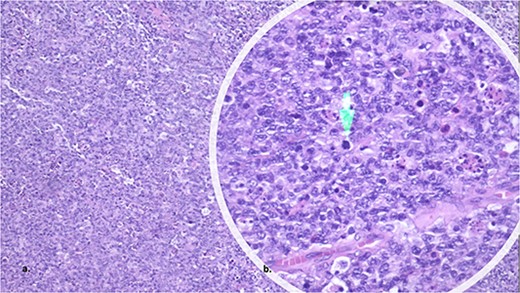

The anatomopathological examination of the colon demonstrated a lymphoproliferative lesion of large and atypical cells with necrosis and hemorrhage, suggesting a high-grade non-Hodgkin’s lymphoma (Fig. 2a and b). Immunohistochemistry of the lesion resulted in CD20, MUM1, BCL2 and BCL6 positive markers (Fig. 3a–d), compatible with DLBCL of the non-germinative center type. In the postoperative period, the patient had no complications and was discharged in 1 day. Then, the patient began her first six chemotherapy courses with cyclophosphamide, doxorubicin HCl, vincristine and rituximab (R-CHOP) every 21 days.

The histopathology showed a lymphoproliferative lesion of large and atypical cells with necrosis and hemorrhage, suggesting high-grade non-Hodgkin’s lymphoma.